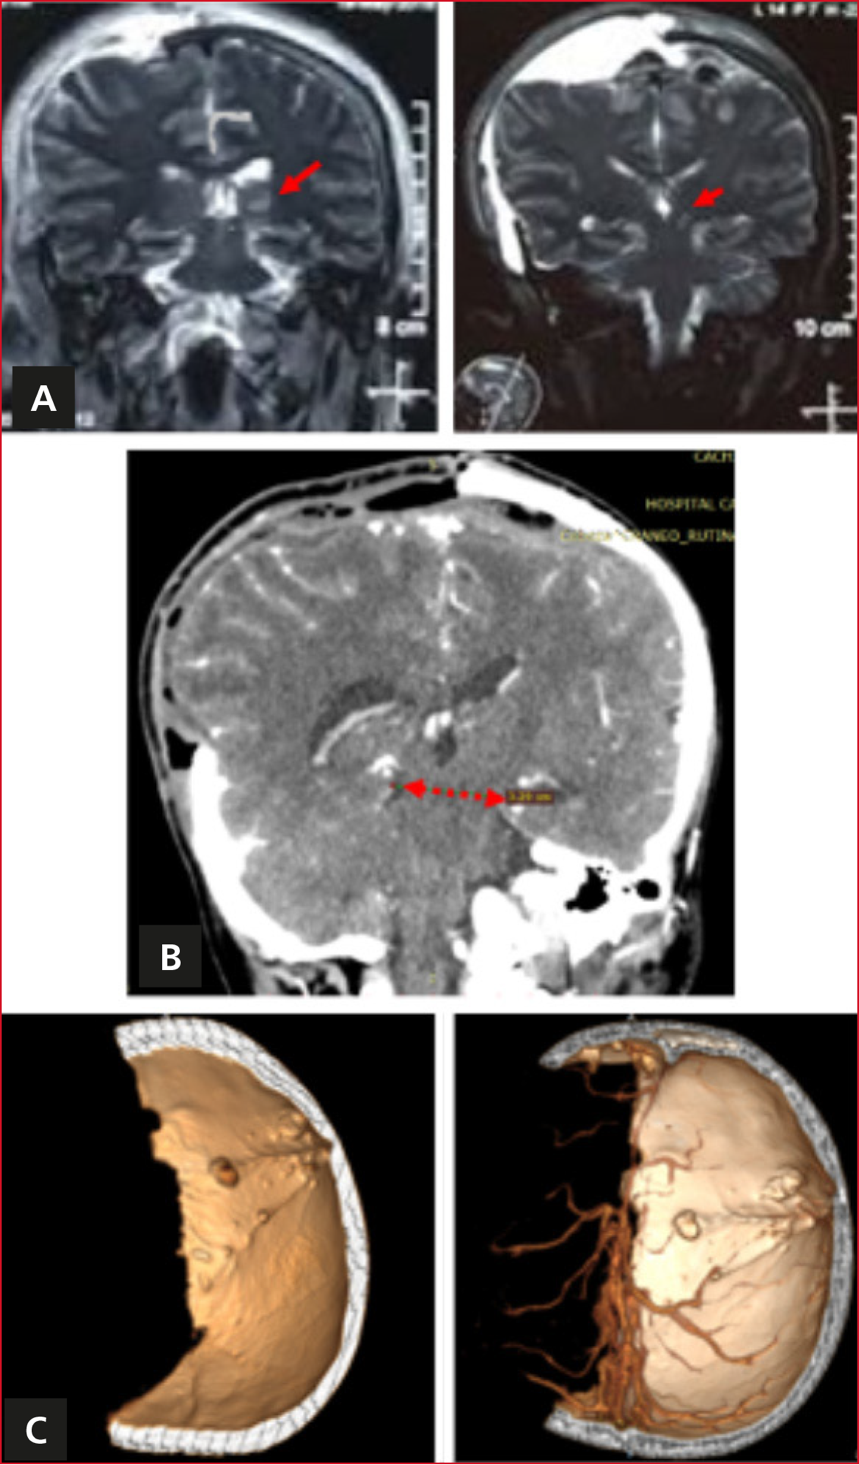

En el período posoperatorio inmediato, el paciente cumplió 72 h de neuroprotección y neuromonitorización. La anisocoria revirtió, se produjo la apertura ocular espontánea, localizando dolor con movimientos completos en el hemicuerpo izquierdo e incompletos con el hemicuerpo derecho al estímulo nociceptivo central O4V1TM5 ECG10T. En la imagen posquirúrgica, se observaron cambios de intensidad en la vía piramidal (Figura 3).

Figura 3. Imagen del estudio del fenómeno de Kernohan-Woltman. A. Resonancia magnética ponderada en T2, corte coronal, vía piramidal. Aumento de la señal en la vía piramidal izquierda (muesca de Kernohan). B. Tamaño de la hendidura tentorial medido entre dos crus cerebri: 3,29 cm. C. Reconstrucción topográfica tridimensional. Faltante óseo derecho hasta la línea media, ausencia de sistemas diploicos de Paccioni parietales derechos.

La etiología del fenómeno de Kernohan-Woltman no está aún aclarada, no todas las lesiones supratentoriales con herniación encefálica presentan este fenómeno, incluso ocupaciones pequeñas han sido suficientes para producir el fenómeno de Kernohan-Woltman.5 Los factores de riesgo propuestos son: agujero tentorial de Paccioni estrecho.5 Existen pocos estudios de antropometría del tentorio que tengan en cuenta dos medidas axiales: la distancia entre el borde superoposterior del dorsum sellae en el plano mediano y el ápice de la hendidura; si mide <48,7 mm se considera corto.6 La otra medida es el ancho máximo de la hendidura, se considera estrecho a uno <27,6 mm;6 sin embargo, no existe medida definida de la dimensión entre las crus cerebri de ambos lados en el plano coronal que es de interés en la imagen del fenómeno de Kernohan-Woltman; otro factor estudiado es la situación de las fibras motoras que no se cruzan en las pirámides bulbares como lo son las que pertenecen al tracto corticoespinal anterior7 y los cambios de presión contralateral creando herniación no local encefálica.3 En el caso, se observa una distorsión anatómica entre el mesencéfalo y la hendidura de Paccioni, la disposición del tronco está lateralizada hacia la izquierda, se observa “un mesencéfalo estrellado” (Figura 3).